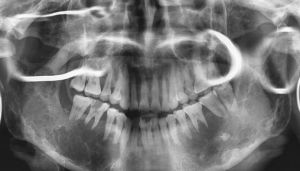

CT檢查1、X線檢查:X線攝片示頜骨膨隆,不規則多房性囊性透光影像,此影像邊緣不光滑,有半月狀切跡,分房大小懸殊,波及牙槽骨者可有明顯的“根尖浸潤征”--牙根尖的牙槽突骨質呈不規則的破壞與吸收,牙根可呈鋸齒狀或截斷樣吸收,如有迅速長大同時伴疼痛潰瘍等症狀,X線表現骨間隔破壞消失,呈斑點狀影時,應疑有惡性變。

4.X線攝片示頜骨膨隆,不規則多房性囊性透光影像,此影像邊緣不光滑,有半月狀切跡,分房大小懸殊,波及牙槽骨者可有明顯的“根尖浸潤征”--牙根尖的牙槽突骨質呈不規則的破壞與吸收,牙根可呈鋸齒狀或截斷樣吸收。

5.如有迅速長大同時伴疼痛潰瘍等症狀,X線表現骨間隔破壞消失,呈斑點狀影時,應疑有惡性變。